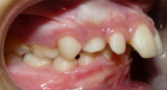

1 Protusión dental

Los dientes superiores sobresalen demasiado, habiendo riesgo de fractura por traumatismo.